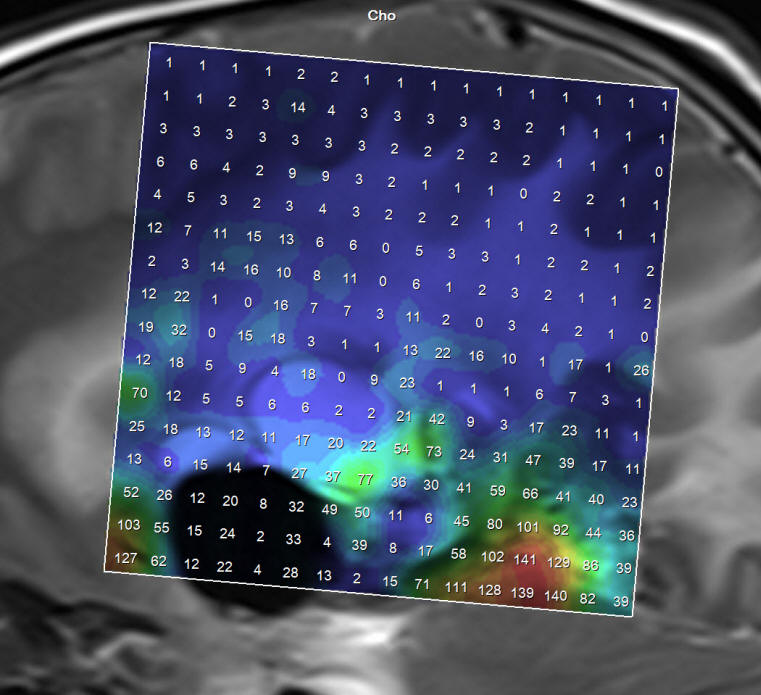

The patient was sent for new MRI of the brain with contrast with MRA of the brain and spectoscopy, DTI and functional MRI and done the same day. The results of investigations shown in Fig. 1-6, listed below.

Figure-1: Choline still high in some places confirming the recurrence of the tumor.

Figure-3: Choline to NAA ratio distribution.

Figure-7: Intraoperative spectroscopy showing remnant of active lesion below the cystic lesions, which are abutting the internal capsule. During surgery we use saline and the air come to fill the cavities and an error message coming out during spectroscopy telling that fluid suppression is an adequate. Despite this fact it is possible to catch the active remnants and establish the fluid content of the cysts.